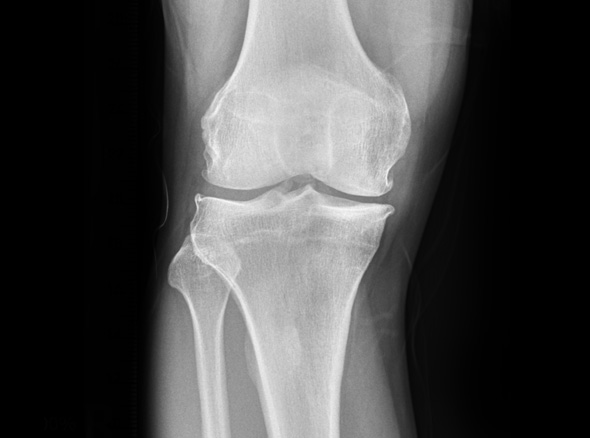

한국인의 대부분에게서 무릎 내측에 무릎 관절염이 발생됩니다.

관절염의 수술적 치료로는 인공관절 수술이 가장 흔하지만, 인공관절 수술을 할 만큼

연골 손상이 심하지 않다면 내측으로 치우친 체중 부하를 정상적인 외측 관절로

이동시키는 ‘무릎관절 교정 절골술’을 시행합니다.